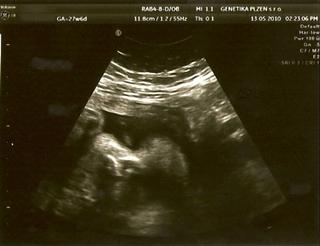

Dneska jsem byla znovu na tom 3D UTZ a miláček náš maličkej (zase tak maličkej není, dle MS 27+6 ale dle UTZ 29+0 a odhad váhy 1300g 😵 ) úžasně spolupracoval, takže teď jdu naskenovat fotečky a za chvíli vám je ukážu 😵

tak naskenováno 😵

Tak ty fotky jsou absolutně boží!!!!

Micha, fotečky Vojtíška jsou naprosto úžasné 🙂 Moc mu to sluší... To byl zážitek, co?